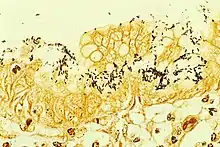

| Immunohistochemical staining of H. pylori (brown) from a gastric biopsy | |